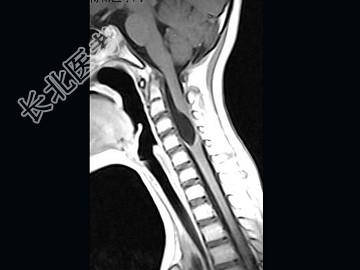

- 单项选择题女,9岁, 颈部疼痛、活动受限2个月,MRI检查如图, 最可能的诊断为 ( )